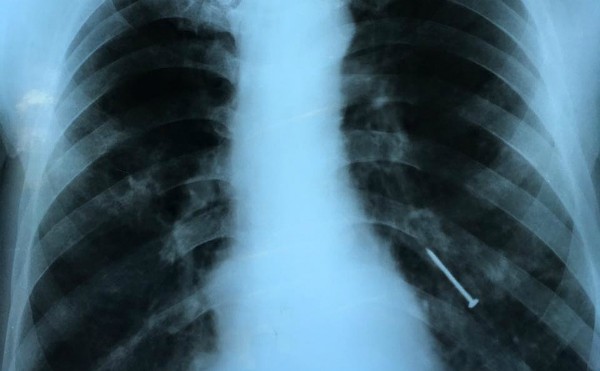

Thông tin từ VTV cho biết, vừa qua Bệnh viện Chợ Rẫy đã tiếp nhận bệnh nhân tên L.Q.H. (55 tuổi) vào viện trong tình trạng ho liên tục 4 tháng qua, có lúc ho ra máu. Kết quả chụp CT cho thấy, bệnh nhân có dị vật nằm ở phế quản thùy dưới bên trái phổi.

Ngay lập tức, các bác sĩ Khoa Nội soi đã tiến hành nội soi bằng ống mềm, gắp dị vật là cây đinh sắt đã gỉ ra khỏi phế quản của bệnh nhân.

Hình ảnh X-quang cây đinh nằm ở phế quản bệnh nhân. Ảnh: V.T.

Trao đổi với Vnexpress, bệnh nhân cho biết, do hoàn cảnh khó khăn nên ông H. phải đi biển sửa tàu thuê. Cách đây 4 tháng ông trong lúc đóng đinh vào thân tàu, ông há miệng và không ngờ cây đinh văng vào miệng rồi chui vào phế quản. Từ đó ông ho liên tục nhưng không có tiền đi viện. Gần đây tình trạng ho chuyển nặng, nhiều lúc ho ra máu nên ông mới vào bệnh viện thăm khám.